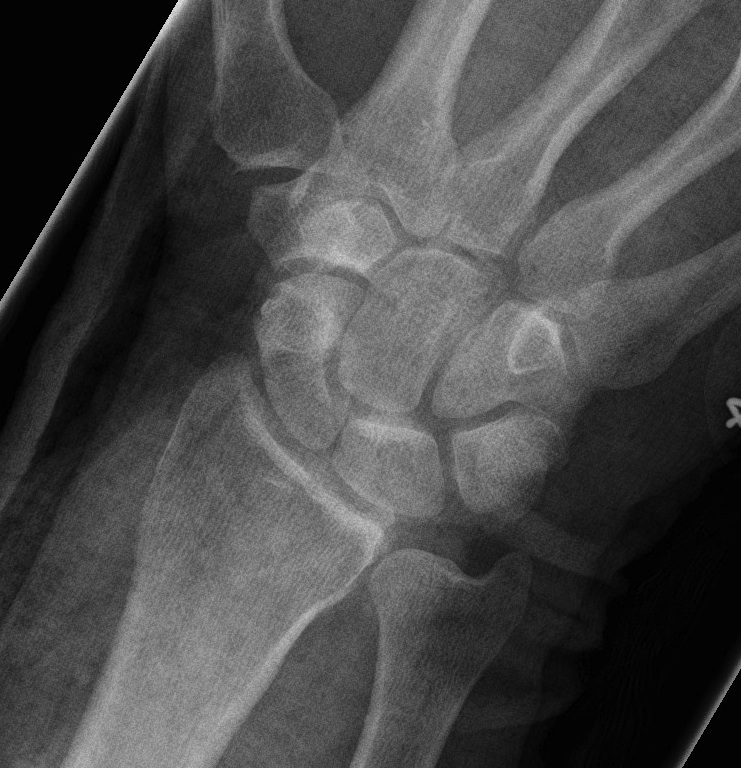

X-ray

Disruption of Gilula's 3 smooth carpal arcs

Progressive Injury

1. Capitate dorsal

- lunate remains with radius

- lunate looks triangular on AP

2. Lunate dislocates

- usually volar